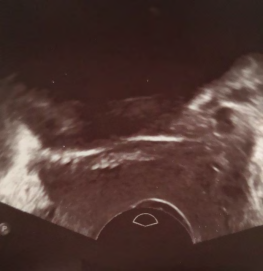

泌尿妇科问题影响着全世界女性的身心健康。不同国家、不同地区的治疗存在差异。国际妇产科内镜协会-泌尿妇科分会希望本文可以为临床工作提供一些建议从而获得最佳诊断,进而使患者获得最佳治疗。SIGE(国际妇产科内镜协会)根据不同地区、不同国家制订相应的治疗。 盆底缺陷是一种良性疾病。作为临床医生,除考虑疾病症状外,还应尽最大努力减少治疗副作用的发生。长期以来,盆底重建手术主要基于盆底解剖结构的改变,治疗的重点是在手术前后进行POP-Q分期。但是近年来,治疗的重点更多地向患者的“功能性”临床变化和患者满意度评分上转移(1-6)。 21世纪的前十年,盆底缺陷治疗的重点是寻求新的手术材料和修复方式来提高治疗效果。但是,新的手术材料有时会出现较严重的并发症,因此,目前很多国家严格限制、甚至禁止使用。所以,临床工作中获得更精准的诊断、向患者询问其主观症状变得尤为重要,这有助于为患者制订个性化治疗方案。对于无症状患者即使有明显缺陷也不建议手术治疗。 其中,尿失禁大多与盆底功能障碍相关,应指导患者记录一周排尿日志,以便评估患者术后压力性尿失禁恢复情况。也有临床医师倾向于关注患者治疗前后生活质量改变情况。